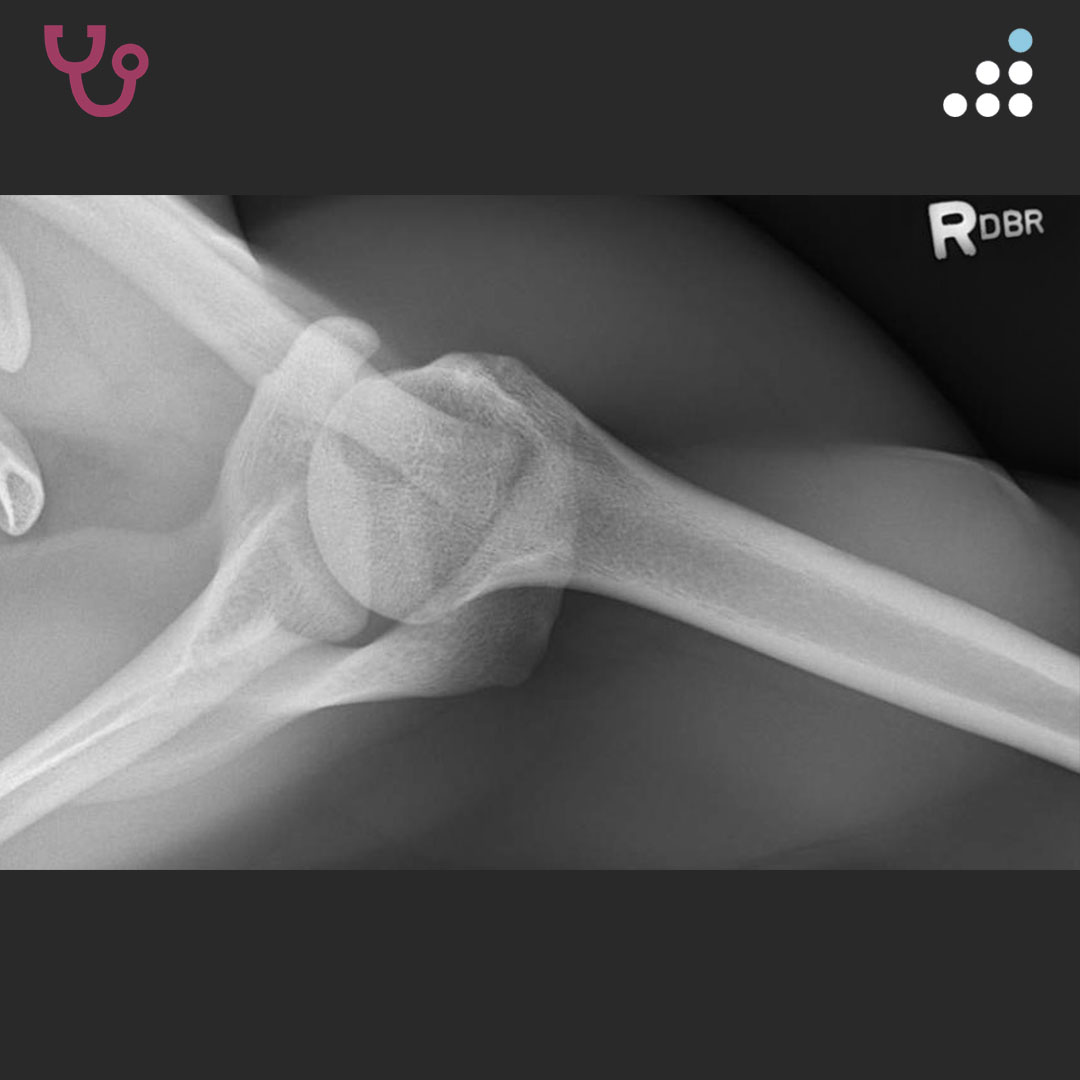

HPI: This is an 18-year-old male who sustained a right shoulder dislocation during a football game on 11/2018. He subsequently had a repeat dislocation in his sleep one week later, which was reduced in the ER. Since then, he has had approximately 7-9 instability events, none requiring formal reduction. He is a senior in high school and desires to play football as soon as he can, with plans to walk on in college.

PMH: Past medical history significant for eczema and sickle cell trait.

PE: On exam, the patient fires deltoid in all three planes. He has full PROM and full 5/5 RTC strength. There is positive subacromial tenderness, negative neer/Hawkins, and no TTP along the biceps tendon. He has a 2+ anterior load shift with guarding and a 1+ posterior load shift. There is pain but no apprehension in all degrees of abduction/ER. He has a negative Obrien’s test and normal resting scapular motion.

SHOULDER INSTABILITY IN 18M